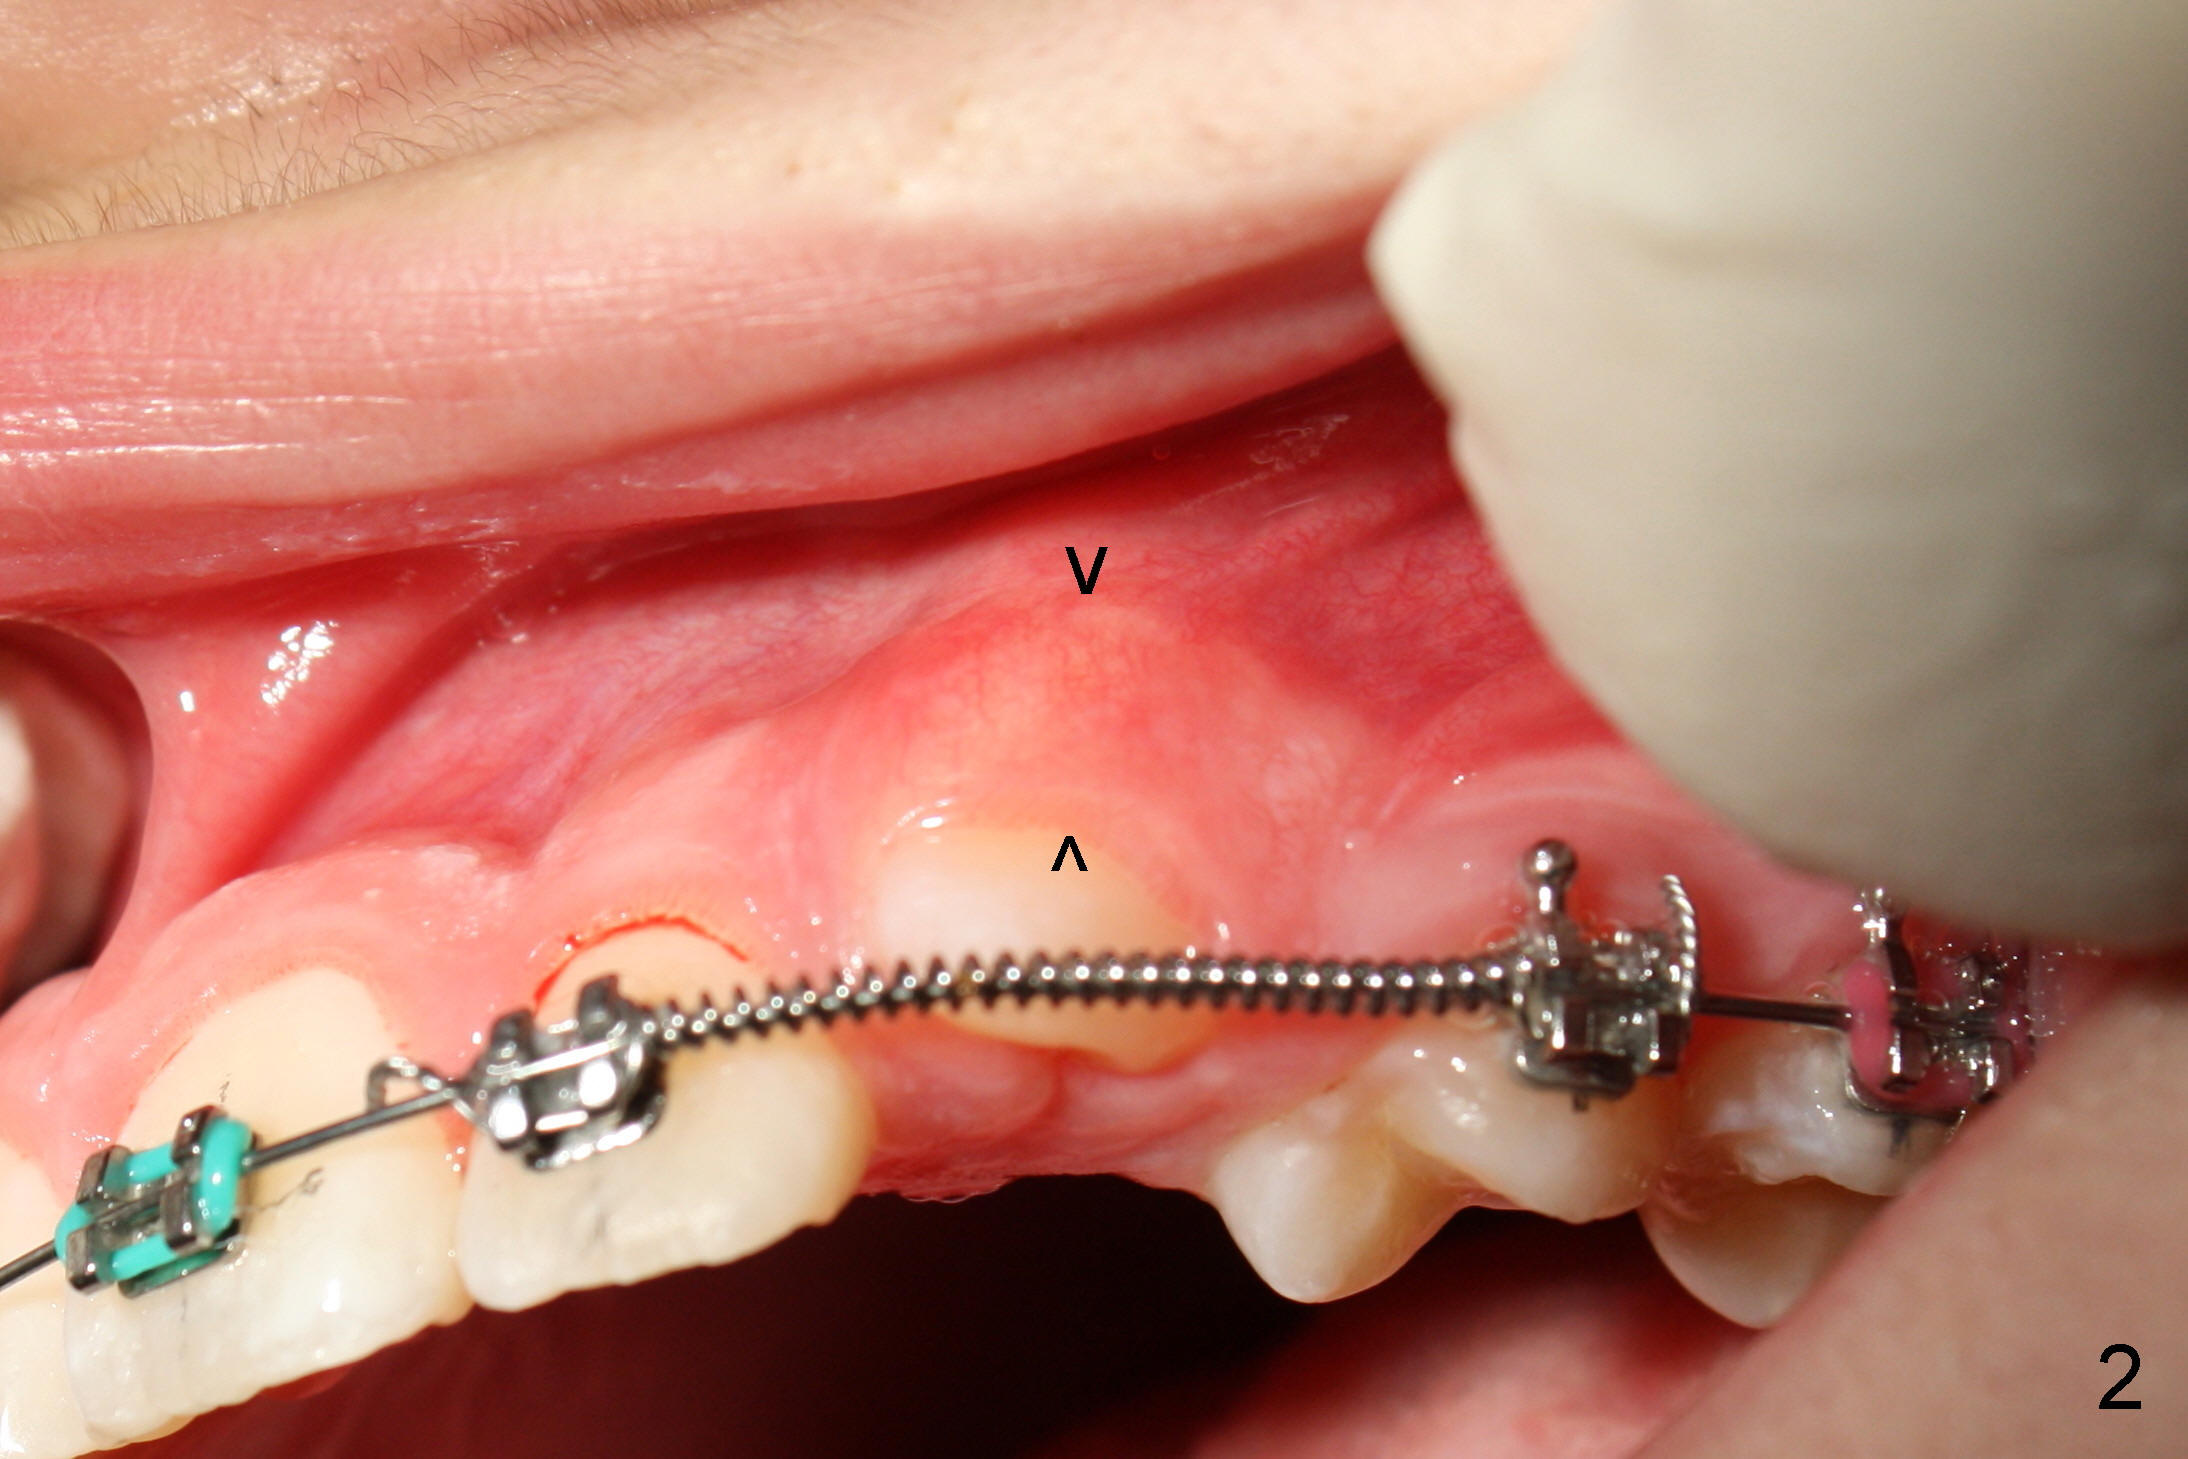

Three months post bracketing, spaces have been gained for U3s, which have erupted initially (Fig.1,2; arrowheads in Fig.2 denote the attached gingiva). UL C has exfoliated. The patient is 13 years old.